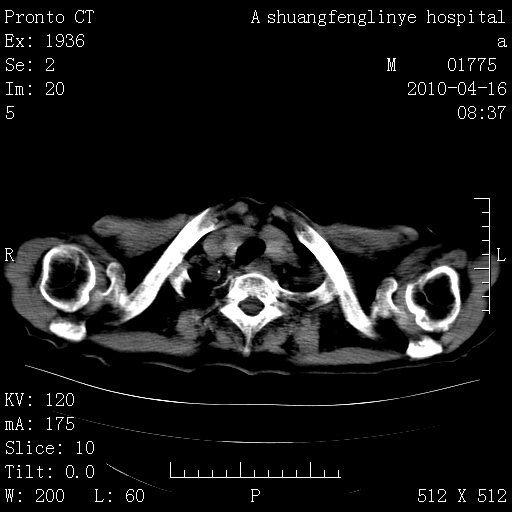

慢支肺气肿,左上陈旧性结核,主动脉冠脉钙化

典型 夹层动脉瘤。 内膜瓣钙化移位

1)左肺上叶结核(纤维、增殖病灶)。2)冠状动脉及主动脉钙化。

1)左肺上叶结核(纤维、增殖病灶)。2)冠状动脉及主动脉钙化。肺动脉高压